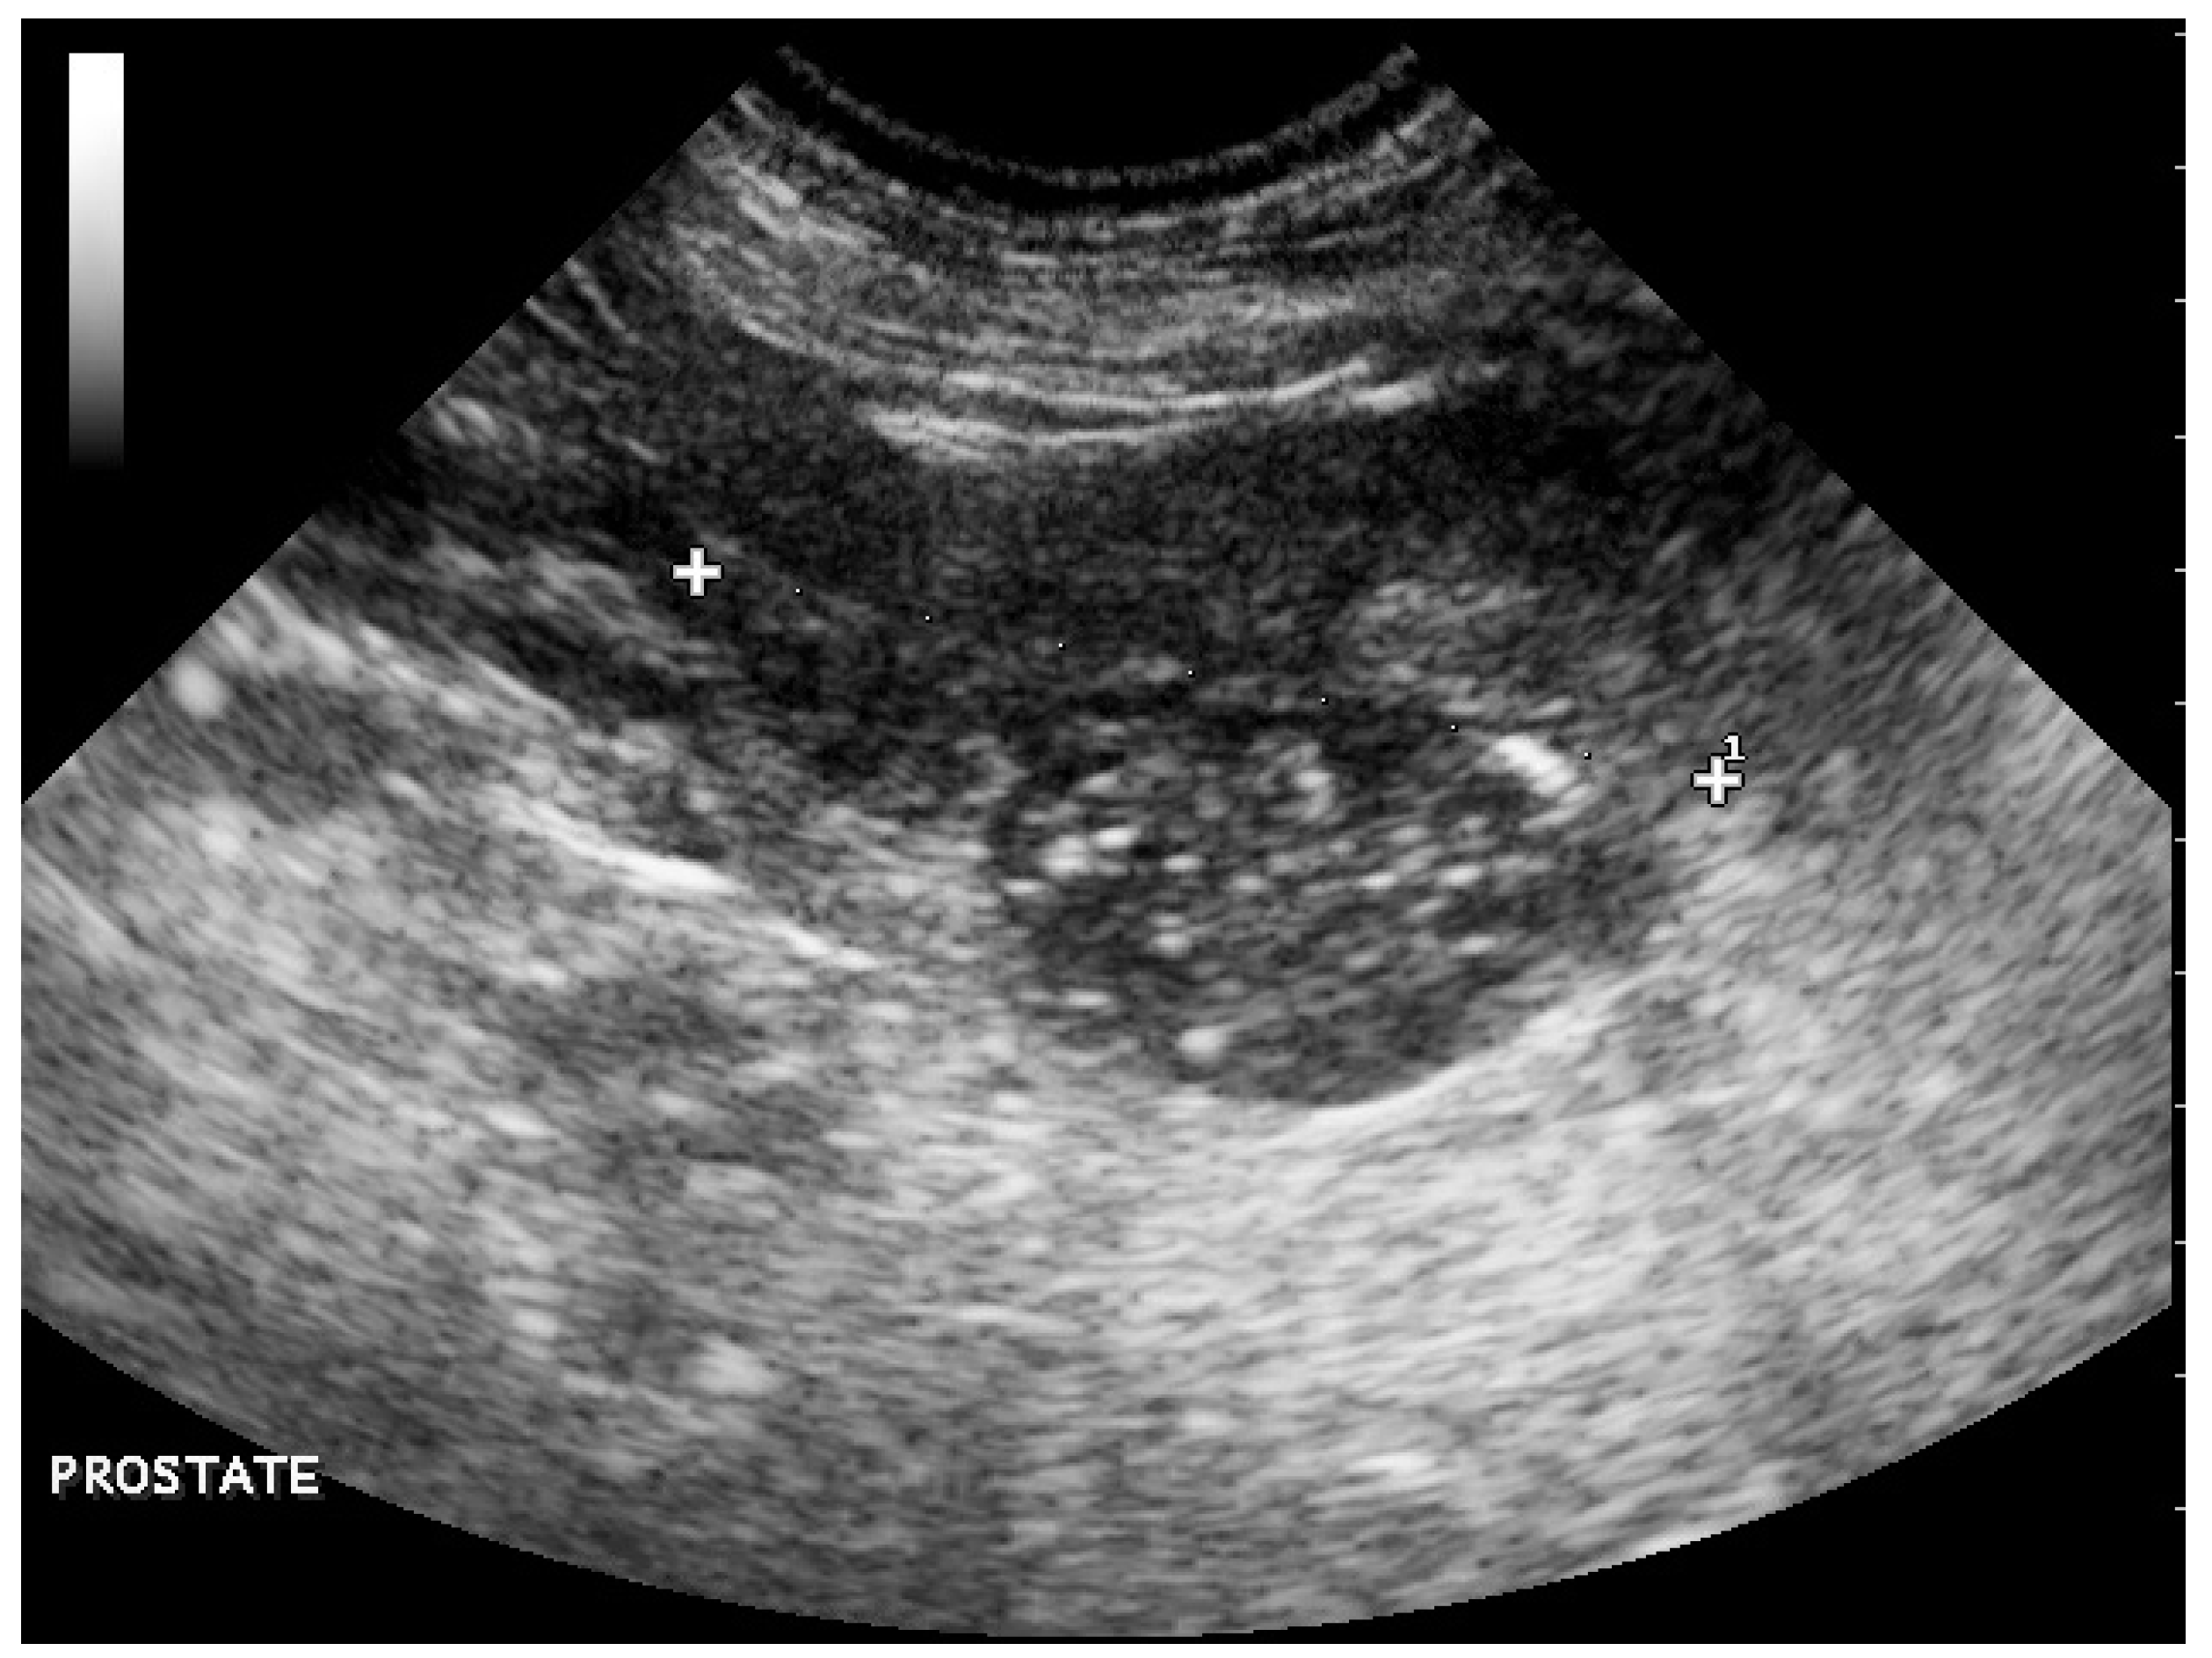

The lateral abdominal radiograph revealed a small calcified prostate, a sublumbar mass (probably lymphadenomegaly) that reinforced the diagnosis of prostate cancer with lymph node metastases. An irregular osteoproliferation of the ventral edges of L5–L6–L7 also suggested tumor invasion. Periosteal proliferative lesions of the pelvis and femurs were consistent with hypertrophic osteopathy (Figure 2). These characteristic lesions were observed on the radius, the ulna, the humerus, the tibia and the calcaneus (Figure 3). Thoracic radiographs revealed lung metastases and pleural effusion.

Figure 3. Other lesions consistent with hypertrophic osteopathy observed on the radius, ulna, humerus, tibia and calcaneus.